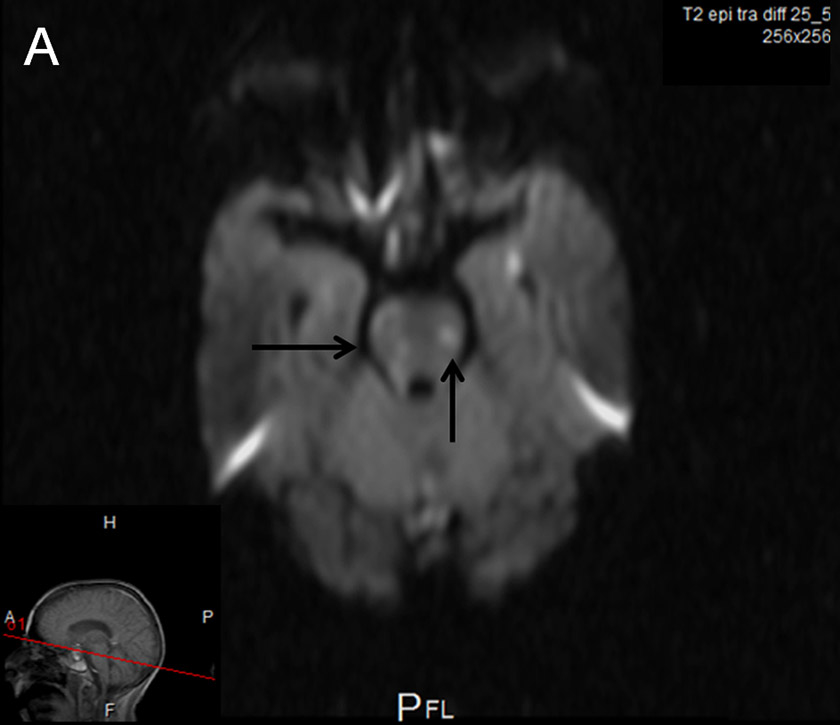

Cerebral MRI.

A, B Axial diffusion-weighted images: Areas of ischaemic necrosis in the pons (A), and thalami and basal ganglia bilaterally (B).

Two days later the patient became drowsy again with signs of upper brainstem dysfunction. Cerebral MRI showed meningeal enhancement and widespread punctate ischaemic-type lesions affecting vascular beds of both carotid and vertebral arteries bilaterally (fig. 1 A–C). MR angiography showed numerous irregularities of the distal arteries, suggestive of vasculitis (fig. 1D). Antibiotic treatment was broadened to include meropenem 3 × 2 g and dexamethasone was restarted but brainstem dysfunction did not improve. Supportive treatment was withdrawn and the patient died on day 21 post-surgery. Subsequent CSF cultures were sterile.